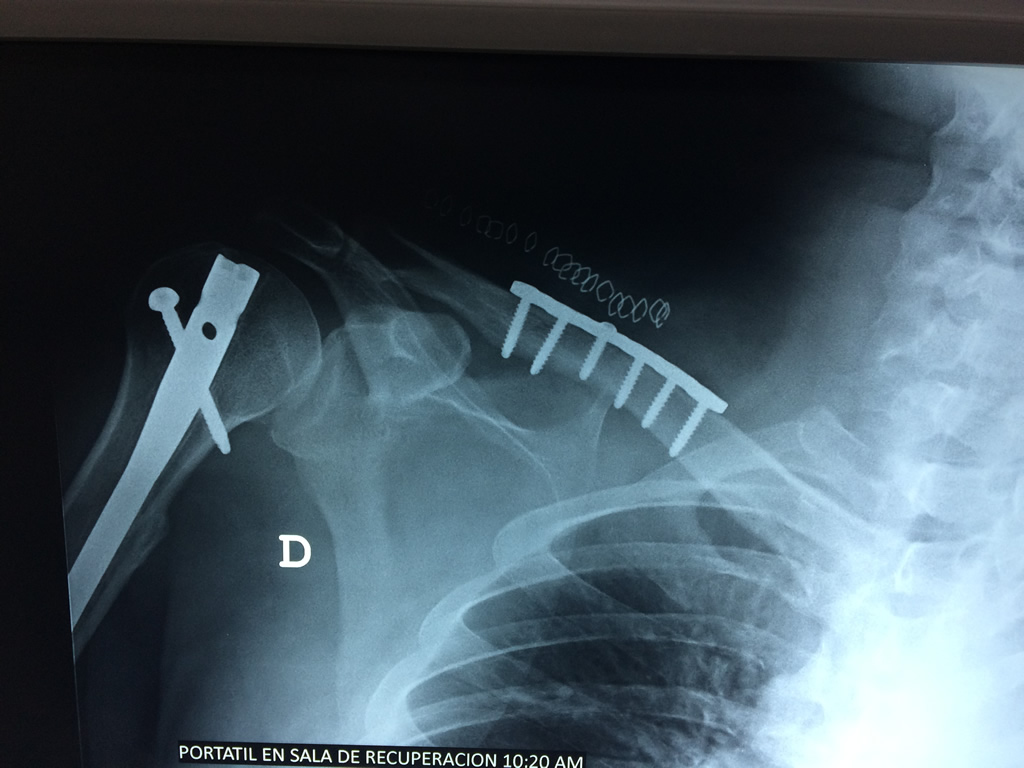

Fémur - Clavícula

La clavícula es un hueso largo, con forma de "S" itálica, situado en la parte anterosuperior del tórax. Junto con la escápula forman la cintura escapular. Se puede palpar por toda su longitud y se extiende del esternón al acromion de la escápula, siguiendo una dirección oblicua lateral y posterior.